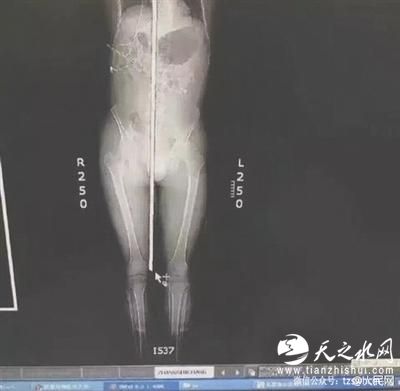

钢筋从右阴囊插入,头顶穿出 图据人民网

经检查发现,该男子意识清楚,鼻腔口腔有鲜血流出。钢筋从男子的右阴囊插入,途经泌尿系统,伤及腹部的肝脾,紧贴心脏和颈动脉贯穿而过。从咽喉直插入口腔,舌头,上颚经鼻腔,插入大脑,最后钢筋从头顶穿出。